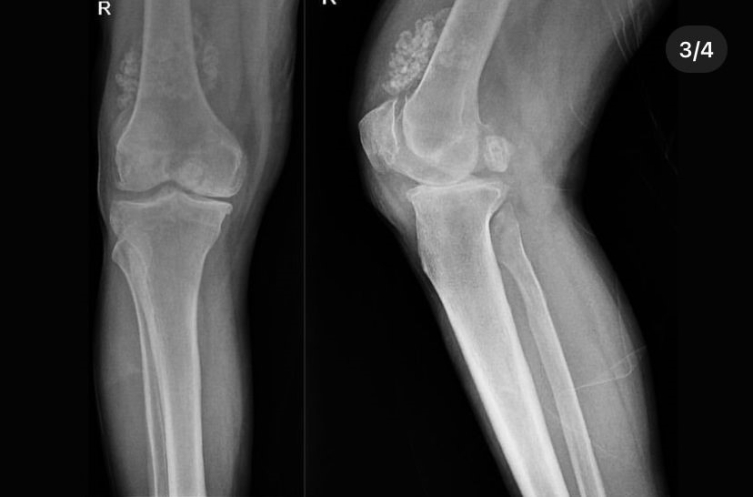

Düzce'de bir hastanın dizinden ameliyatla 41 "eklem faresi" (kıkırdak veya kemik yapısının bozulması sonucu kopan parça) alındı.

Tetkiklerde, hastanın özellikle diz eklemi çevresinde halk dilinde "eklem faresi" olarak bilinen 41 "multipl sinovial kondromatozisi" tespit edildi.